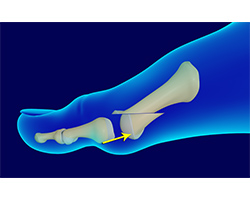

What is Metatarsal Surgery?

Metatarsal surgery is a surgical procedure performed on the metatarsal bones, the long bones in the feet that connect to the toe bones. It is usually performed to correct a bunion deformity and is mainly done on the first metatarsal bone behind the big toe. Surgery on the second to fifth metatarsal bones is usually performed to treat callouses or ulcers at the bottom of the foot.

The metatarsal bones are the five long bones present behind each toe in the foot. These bones help in twisting or movement of your foot and to maintain balance while walking. The bone behind the big toe is called the first metatarsal and the bone behind the little toe is called the fifth metatarsal.